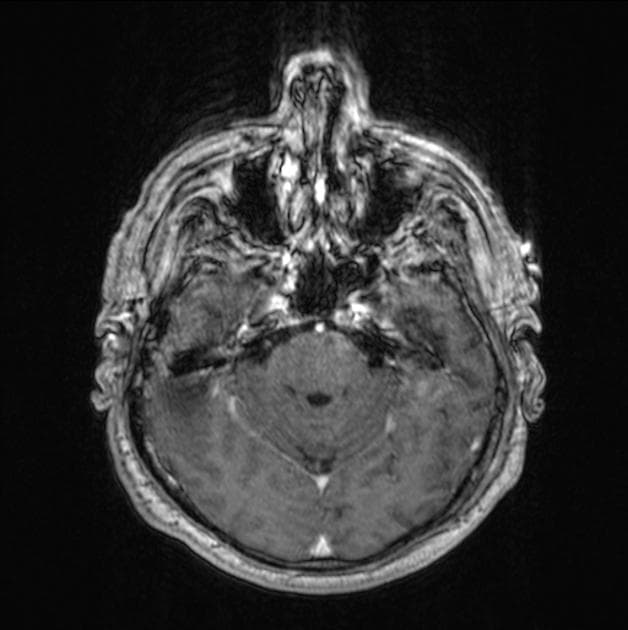

Sagittal T1 C+

MRI sọ não

Có một tổn thương lớn bắt thuốc dạng viền (ring-enhancing) làm giãn cầu não, chủ yếu bên trái, lan vào cuống não trái. Các tổn thương nhỏ tương tự khác thấy ở cuống não phải và nhân nhạt/gai trong của bao trong bên trái, với vùng tăng tín hiệu trên FLAIR nối liền các tổn thương này. Một số ổ giảm giá trị ADC rải rác trong các tổn thương, chủ yếu ở vùng ngoại vi, cùng với thể tích máu não (CBV) tăng nhẹ ở viền tăng quang. Phổ đơn voxel cho thấy đỉnh lactate rõ rệt trong tổn thương cầu não lớn và phổ không bất thường ở vùng nhân nền trái. Các artefact "blooming" ở phần dưới tổn thương cầu não có thể biểu hiện sản phẩm xuất huyết hoặc vôi hóa; đối chiếu với CT trước đó sẽ hữu ích. Phần còn lại của não không có bất thường. Các não thất và bể não nền bình thường. Không có lệch đường giữa (midline shift) hay thoát vị não (cerebral herniation).

Trường hợp này cho thấy tổn thương liên tục ở thân não và nhân nhạt trái/bao trong với nhiều vùng bắt thuốc dạng viền. Hình ảnh và vị trí gợi ý viêm tiểu não – cầu não (rhomboencephalitis) hoặc u thần kinh đệm độ cao, trong đó u thần kinh đệm độ cao được ưu tiên hơn dựa trên bối cảnh lâm sàng. Bệnh di căn được cho là ít khả năng do phân bố tổn thương.